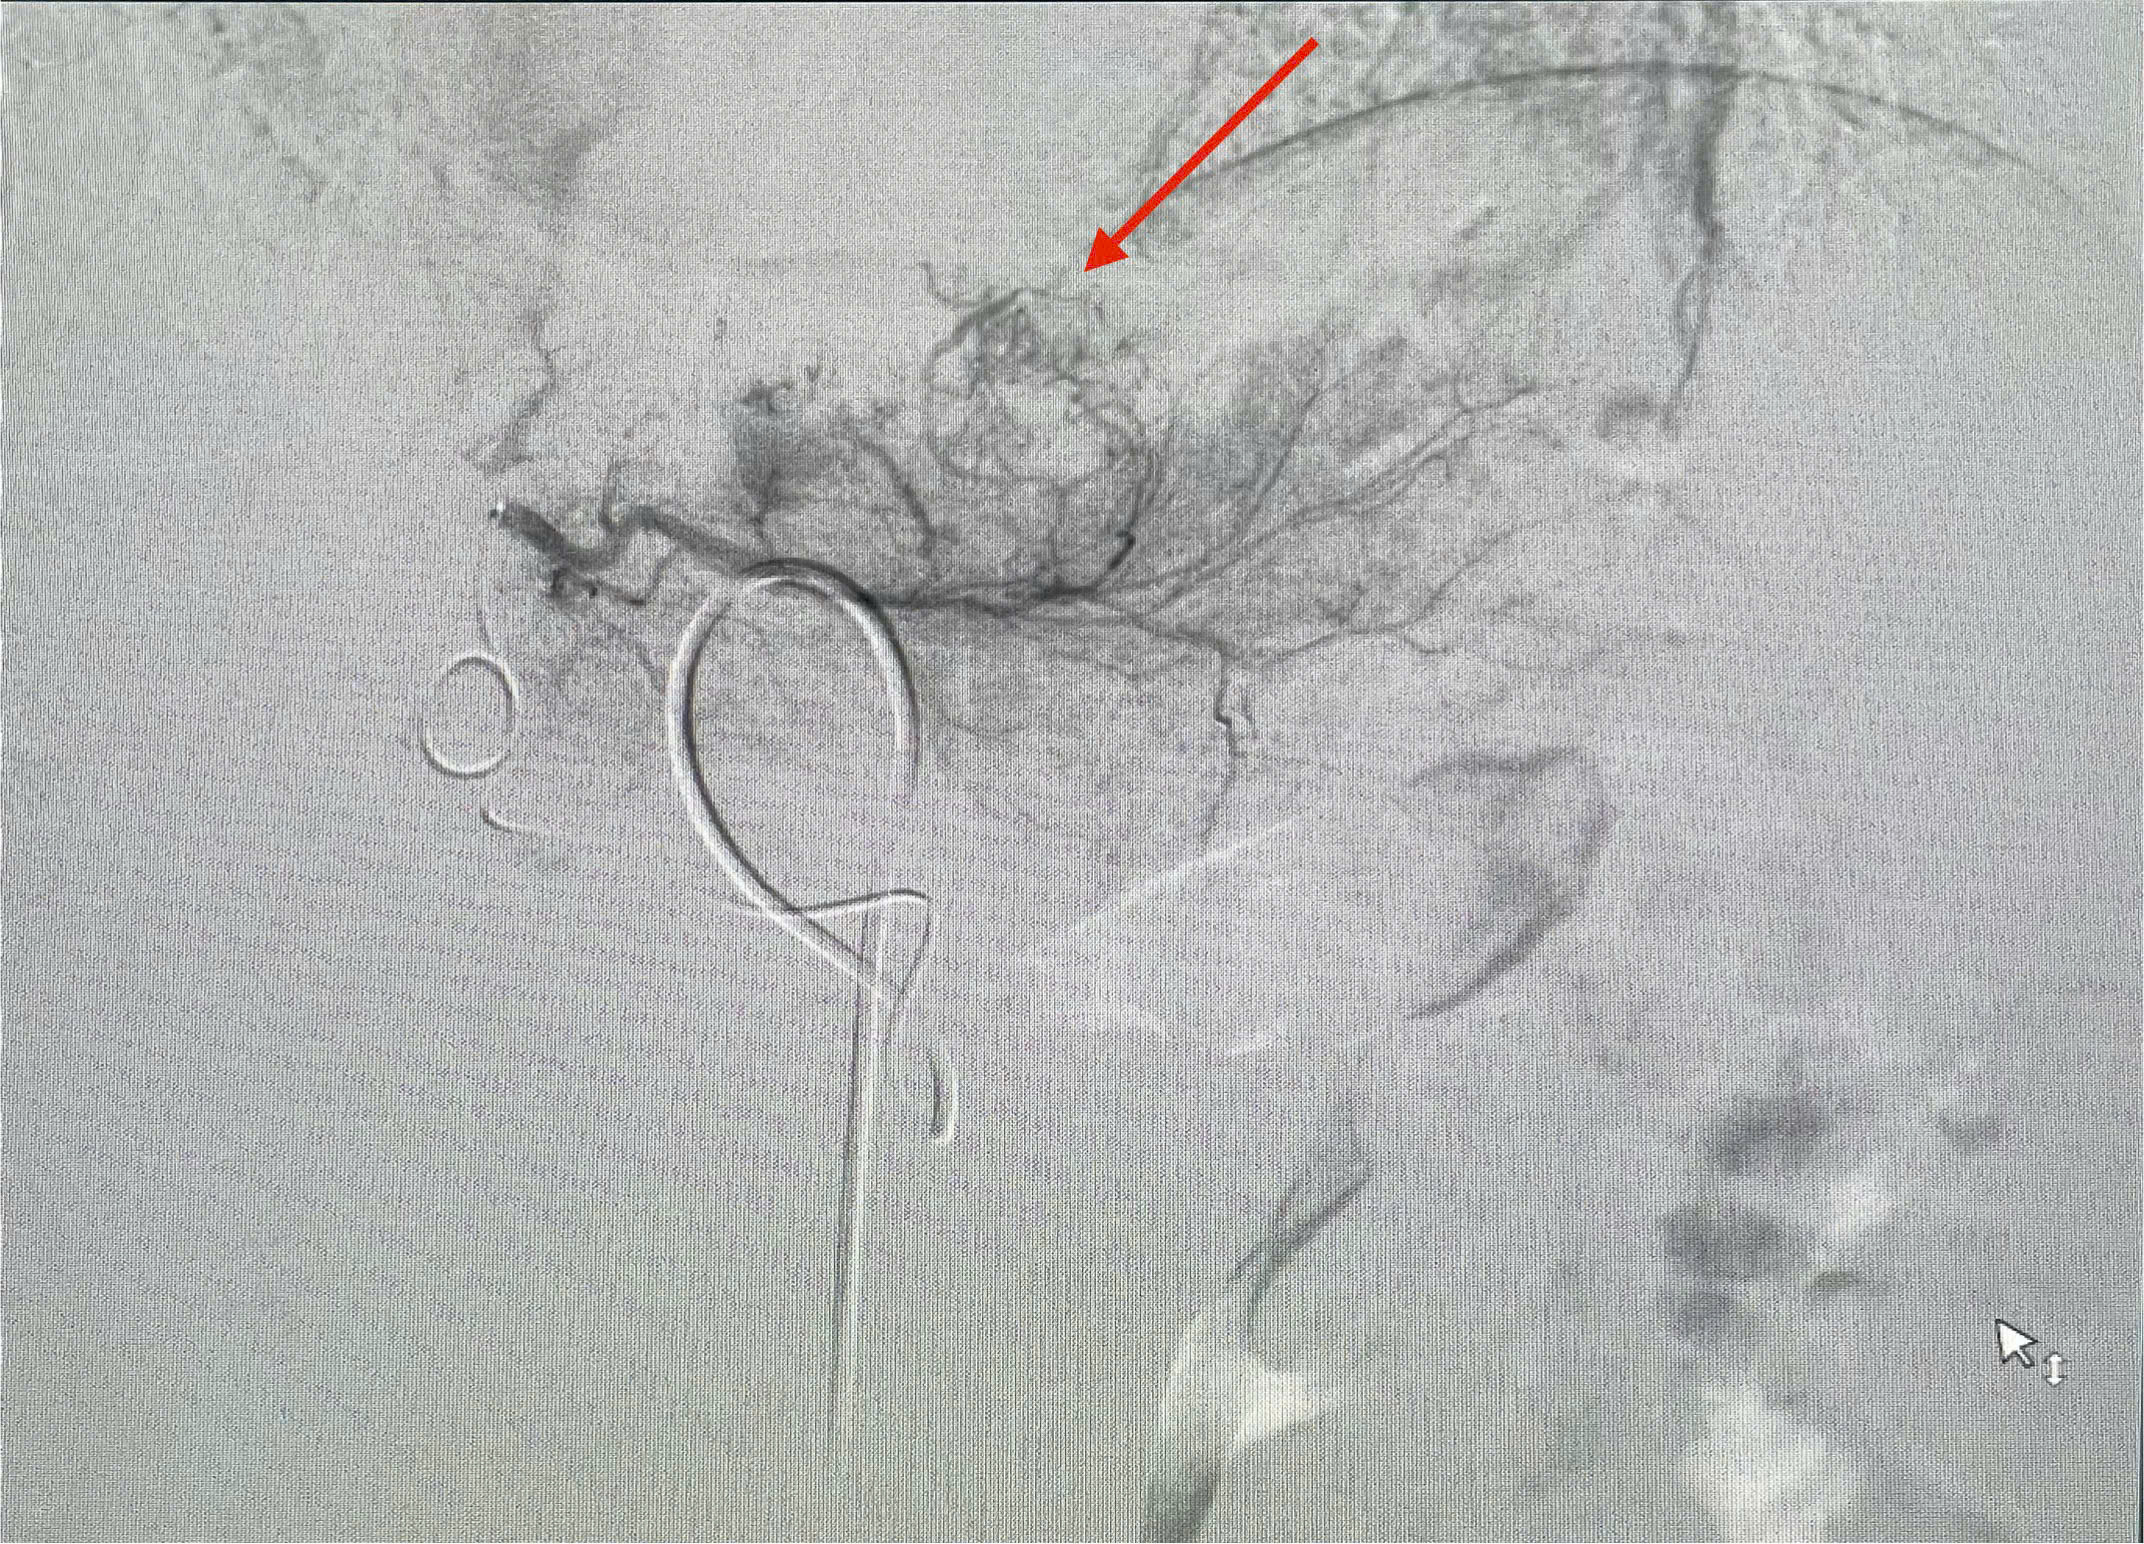

Dưới hướng dẫn của hệ thống máy chụp DSA tiên tiến, hiện đại, giúp bác sĩ tiếp cận và sử dụng các vật liệu thuyên tắc mạch ngắt nguồn nuôi khối u.

Hình ảnh: nút mạch u gan tại bệnh viện